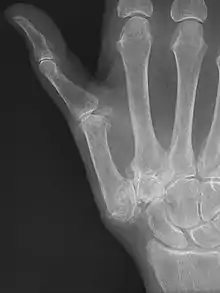

TMC OA is diagnosed based on symptoms and signs.[8] Radiographs can confirm the diagnosis and the severity of TMC OA. Other diagnoses in this region include scaphotrapezial trapezoid arthritis and first dorsal compartment tendinopathy (De Quervain syndrome) although these are usually easy to distinguish.

TMC OA severity was classified by Eaton and Littler which can be simplified as follows:[21][22]

Stage 1:

- slight widening of the joint space

- < 1/3 subluxation of the joint (in any projection)

Stage 2:

- Osteophytes, < 2 mm in diameter, are present. (usually adjacent to the volar or dorsal facets of the trapezium)

Stage 3:

- Osteophytes, > 2 mm in diameter, are present (usually adjacent to the volar and dorsal facets of the trapezium)

- Slight joint space narrowing

Stage 4:

- Narrow joint space

- Concomitant scaphotrapezial arthritis

A simpler classification is no arthritis, some arthritis, and severe arthritis.[23] This simpler classification system omits the potentially contradictory details of the Eaton/Littler classification and keeps scaphotrapezial arthrosis separate.